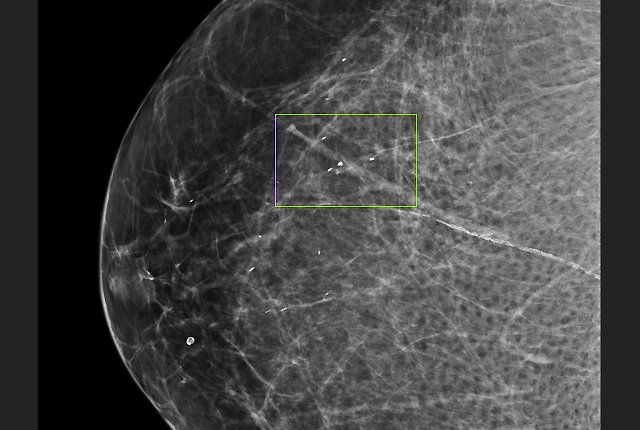

AI has followed that same early path, scoring wins in reader studies. In these studies, a radiologist goes head to head with AI, interpreting a specially prepared set of a couple hundred breast scans that have been goosed with a much higher rate of cancer findings than one would see at a population level.

“If you create a case set of 240, you probably include 100 cancer positives,” Lee explained. “In the real world, cancer-positive cases only account for about five in every 1,000 screenings we do. The radiologists involved know that the case sets include many more cancer findings than would be the case among 240 randomly collected mammogram screenings. Moreover, they know that they’re up against an artificial intelligence system. So the radiologists are more sensitive to detecting cancer.”

Reader studies are designed this way to gather the most possible evidence of AI’s cancer-detection prowess – because improved detection is what the Food & Drug Administration needs to approve an algorithm, Lee said. Unfortunately, this design also overlooks AI’s red flags, which in the real world might contribute to a false-positive reading and a patient being called back for additional tests that cause emotional and financial distress.